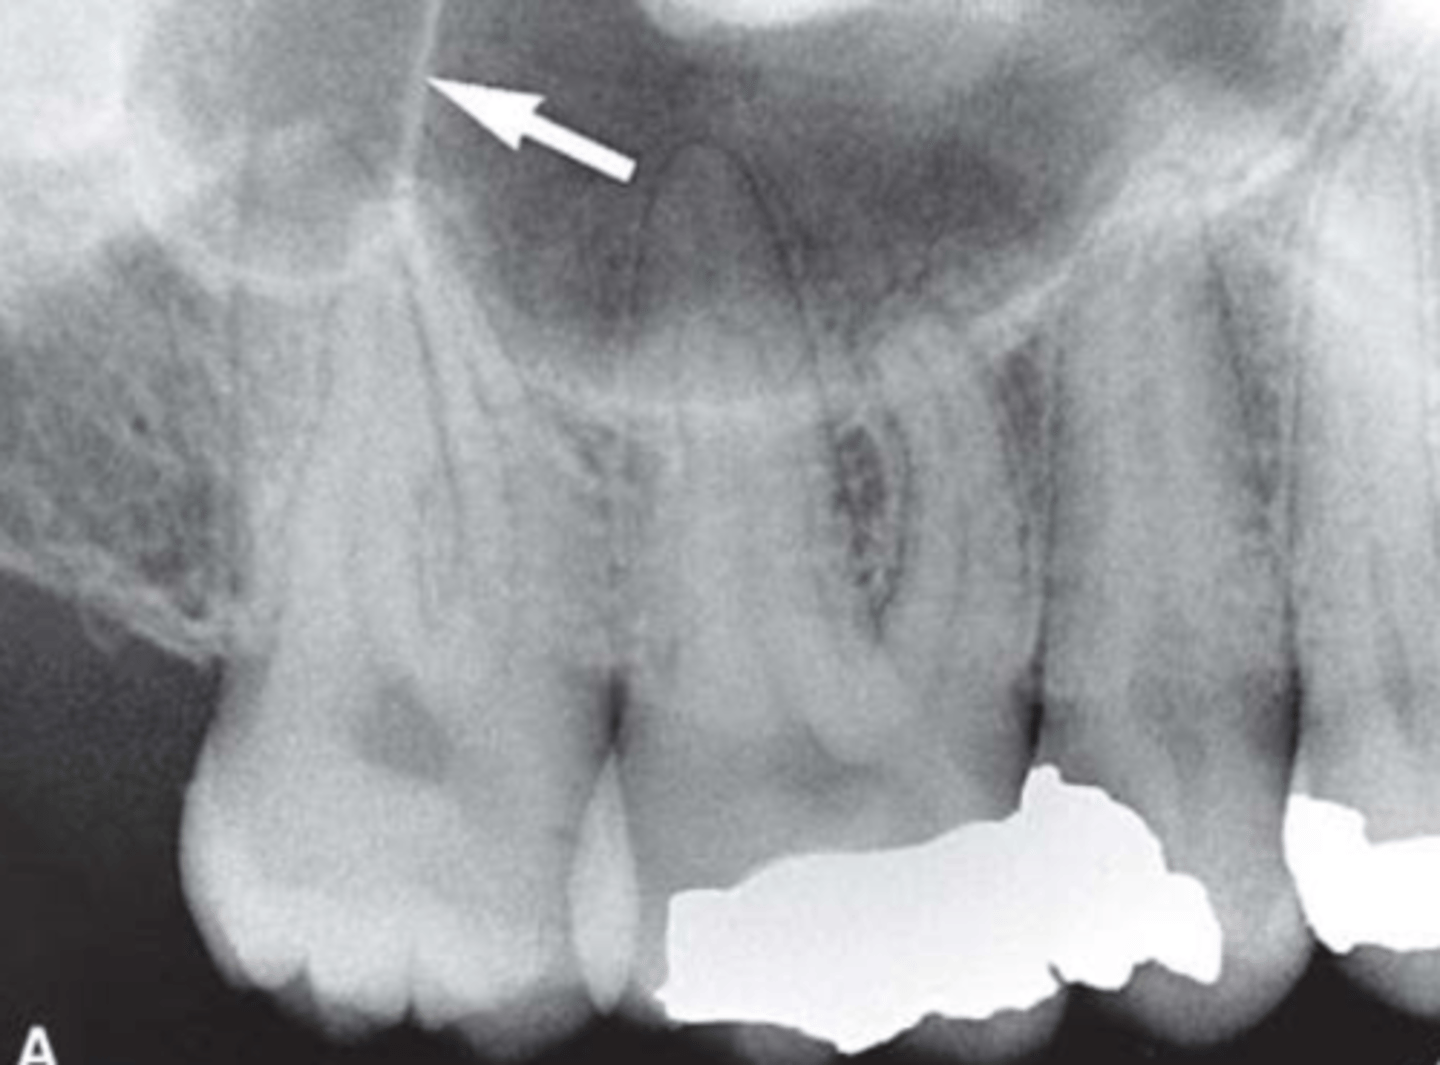

Floor of nasal cavity

Identify the structure

<p>Identify the structure</p>

7

New cards